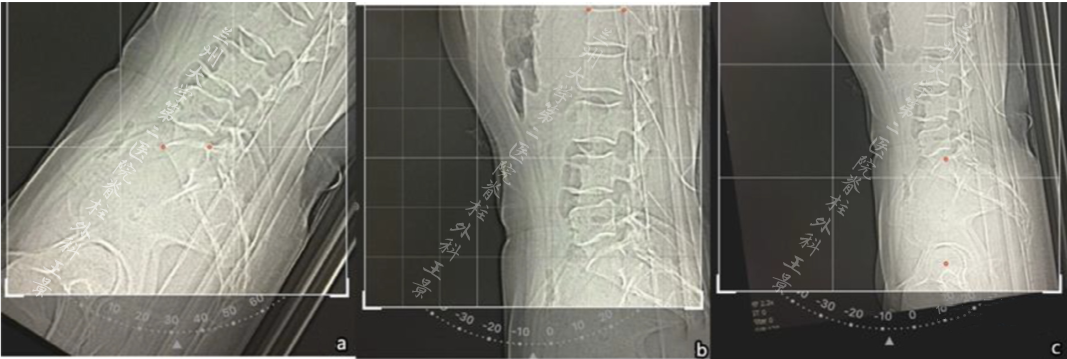

如法炮制,拍照测量脊柱侧弯Cobb角

为方便演示,照片标注上、下端椎终板连线

旋转照片使终板连线和网格线重叠

读出上、下端椎的倾角绝对值

相加后就是Cobb角

这就叫

端椎倾角法快速测量Cobb角